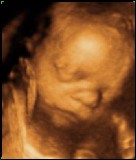

27 Week 3D/4D Scan on 04 May 2006